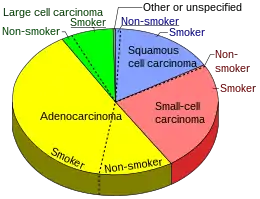

The majority of lung cancers can be characterized as either small cell lung cancer (SCLC) or non-small cell lung cancer (NSCLC). Lung adenocarcinoma is one of the three major subtypes of NSCLC, which also include squamous carcinoma and large cell carcinoma.[15]

Incidence of pulmonary adenocarcinoma has been increasing in many developed Western nations in the past few decades, with a share reaching 43.3% of all lung cancers in the US as of 2012,[40] thus replacing squamous cell lung carcinoma as the most common type of lung cancer. This can be largely attributed to the decreasing smoking rates, which favors the adenocarcinoma histology. Indeed, although smoking is still its strongest risk factor, lung adenocarcinoma is by far the most common among lifelong non-smokers (<100 cigarettes in a lifetime).[41]

- ↑ Smokers defined as current or former smoker of more than 1 year of duration. See image page in Commons for percentages in numbers. Reference:

- Table 2 in: Kenfield SA, Wei EK, Stampfer MJ, Rosner BA, Colditz GA (June 2008). "Comparison of aspects of smoking among the four histological types of lung cancer". Tobacco Control. 17 (3): 198–204. doi:10.1136/tc.2007.022582. PMC 3044470. PMID 18390646.